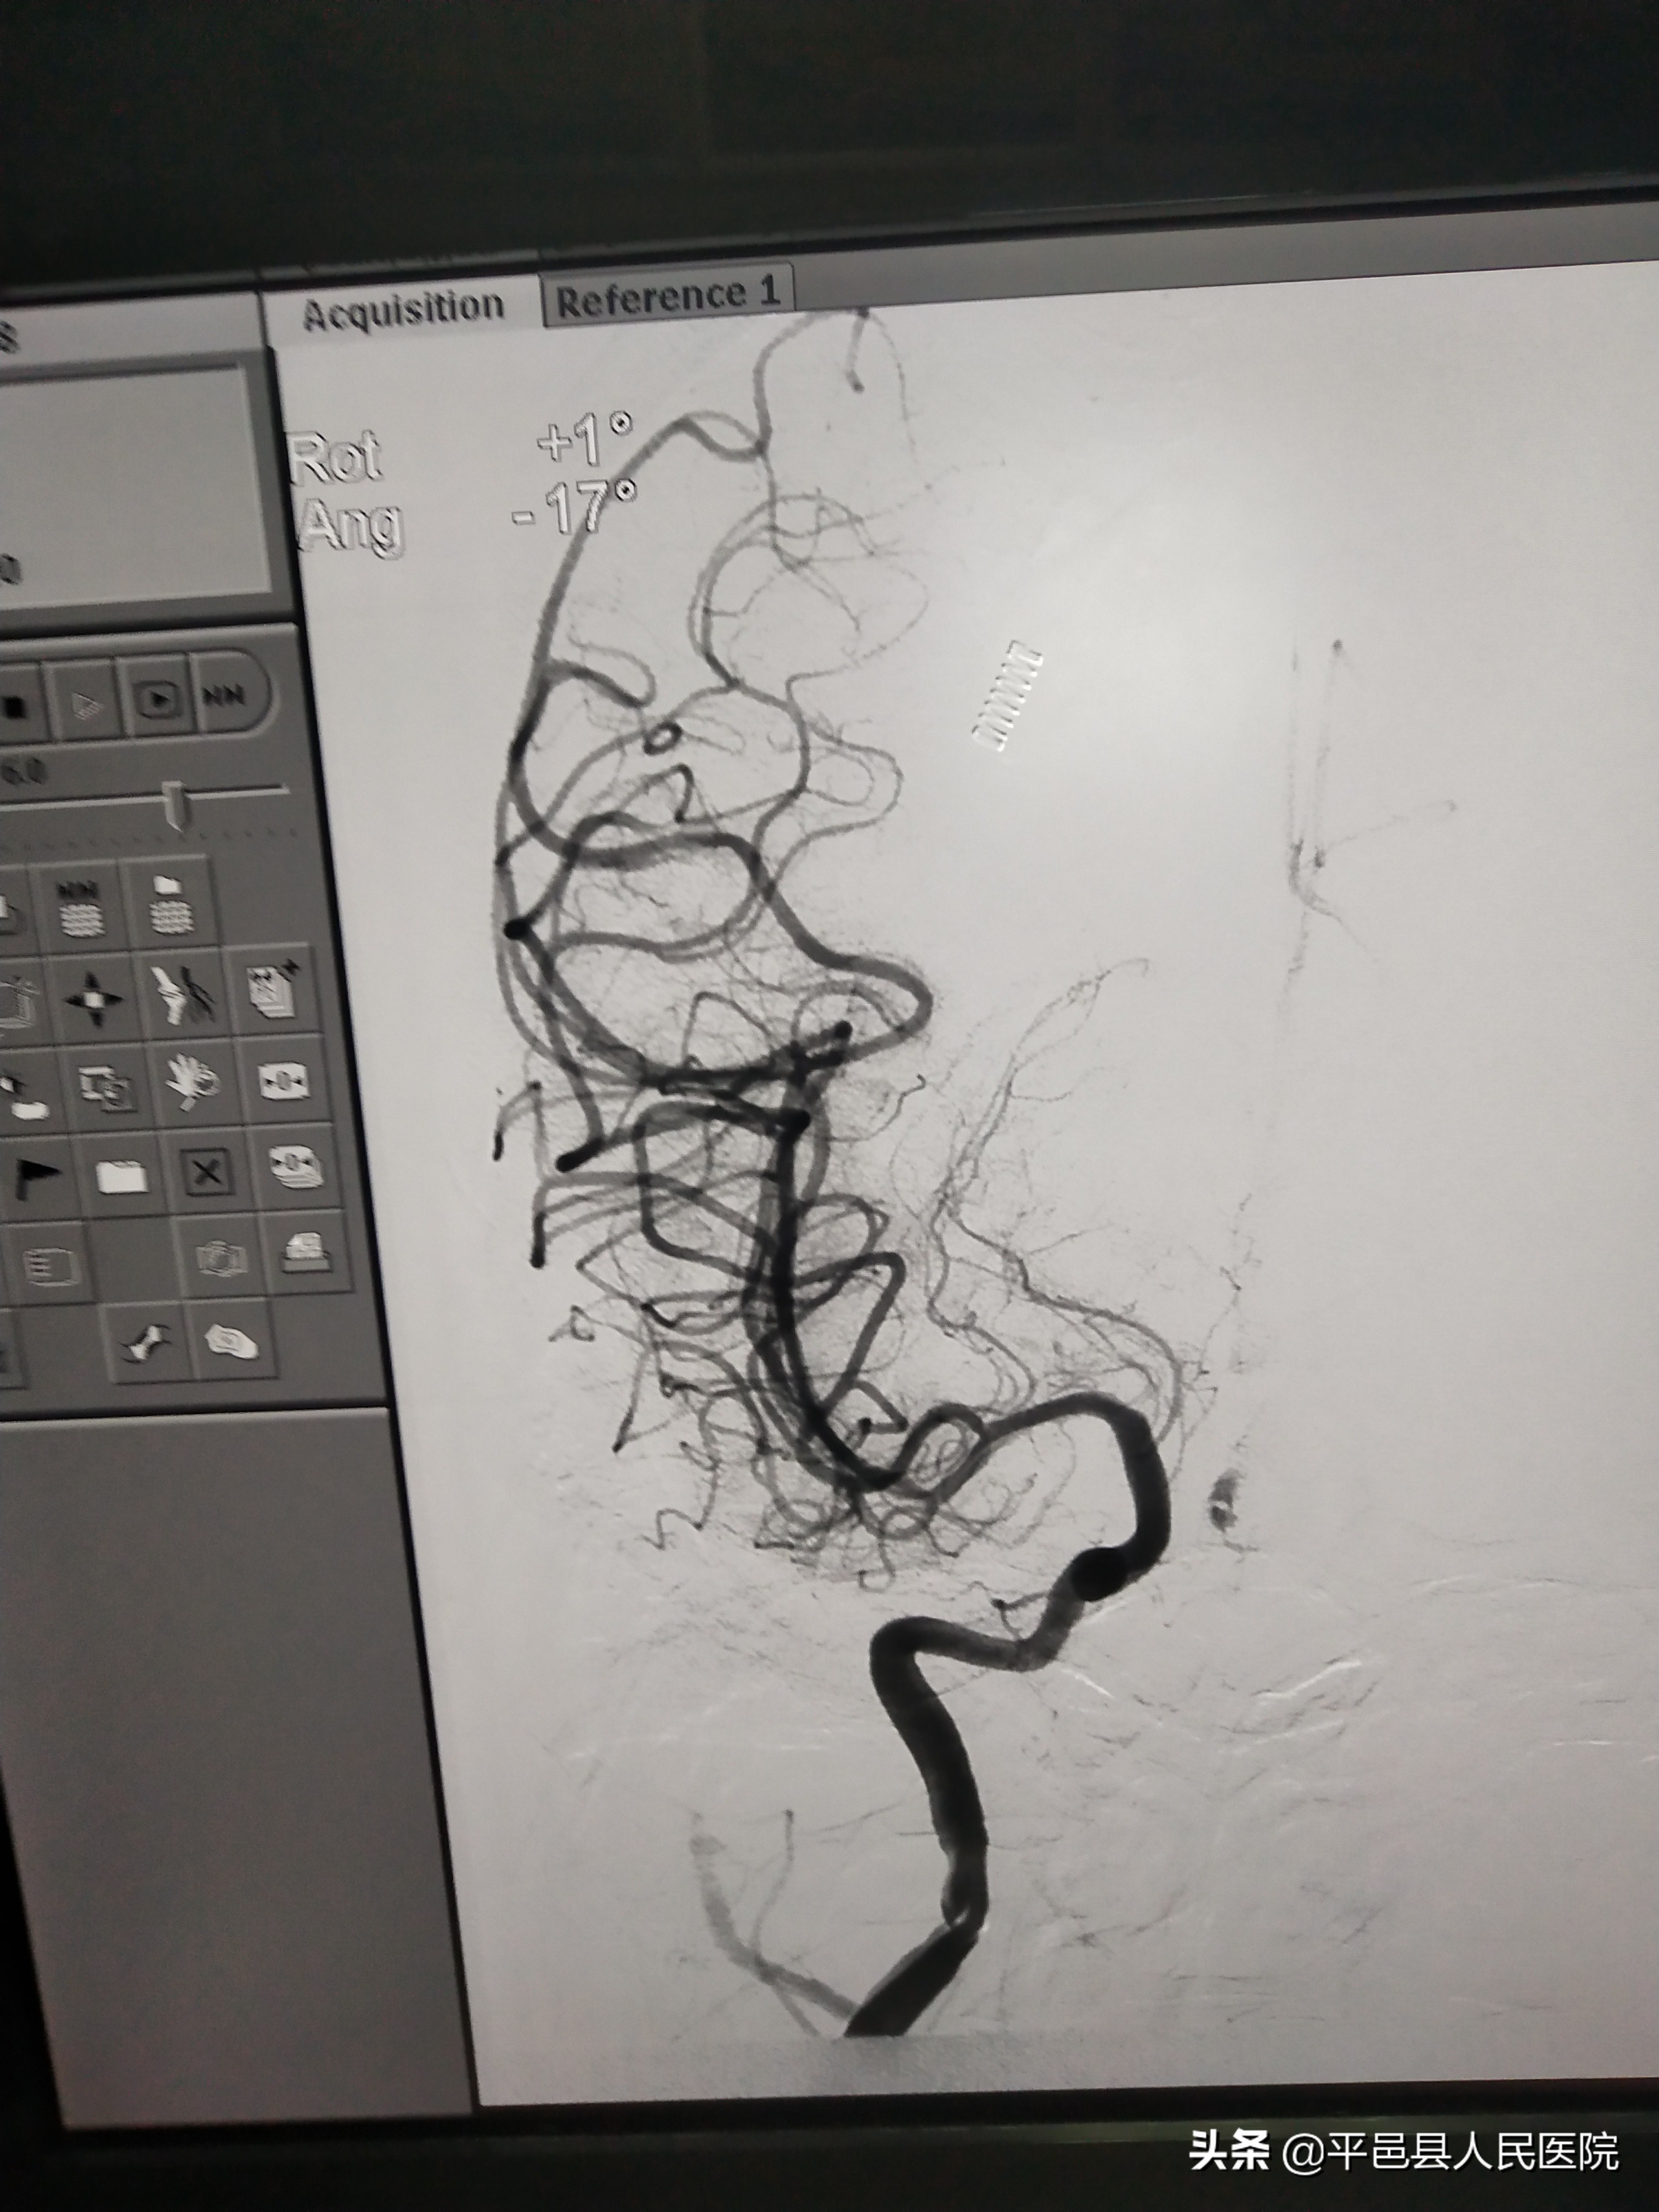

河北来平邑的客商白先生,有高血压病史,因突发意识障碍1小时入院。卒中中心值班医师查体见:深昏迷状态,双瞳孔缩小,对光反射消失,四肢痛觉刺激下均无活动,双侧病理征阳性。急查颅脑CT等相关检查,初步判断为急性脑梗死,考虑为后循环大血管病变,立即给予阿替普酶静脉溶栓治疗,同时与患者家属谈话,建议桥接血管内介入手术治疗。造影发现患者基底动脉主干完全闭塞,基底动脉供应人体脑干、小脑、大脑后部,是生命中枢的血氧养分来源,若不能及时打通,患者必将死亡,为患者紧急取栓治疗,经过取栓支架拉栓和抽吸取栓,病变血管完全再通,达到3级血流,术后复查颅脑CT也未见出血或高灌注脑损伤等并发症,意识清醒。自患者到达医院到血管再通,仅用时2小时45分钟,据患者发病也仅有不足4小时,减轻了脑缺血缺氧坏死的程度,更有利于患者神经功能康复。目前患者语言清晰、身体四肢活动自如。

术前血管堵塞

术后血管再通